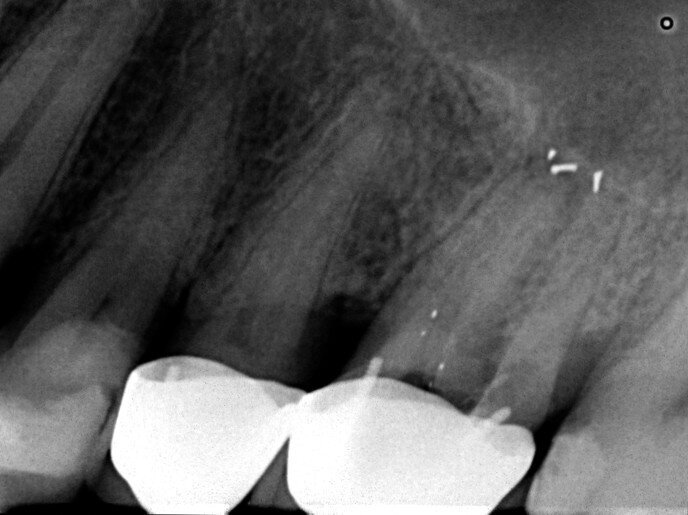

The patient was referred for a dull pain affecting a maxillary molar. On the preoperative radiograph, we could see a diversity of obturation materials, including single cones, resin cement and silver cones, with some of them already fragmented and one piece protruding from the root. Looking closely at the sinus and the sinus membrane, we could see that the membrane had been perforated by the inflammatory/infection process, which had led to sinus infection (Fig. 15).

Under the operating microscope and using ultrasonic and K3XF rotary files (Kerr Dental), I managed to clear the root system of all the previous obturation materials, and placed a dry cotton pellet and temporary cement, as the patient had become tired during this long appointment (Fig. 16). Figure 17 shows some minor debris of silver cones that had passed beyond the mesial apex and using the MacroCannula of the EndoVac, I managed to retrieve one small piece of the silver cone and to complete the chemical cleaning of the root canal system.

Figure 18 shows the immediate postoperative situation, focusing on the obturation of the mesial canals, and a slight improvement of the membrane and the sinus is evident. Figure 19 shows the three-month follow-up with an almost complete closure of the membrane and the bone of the sinus floor.